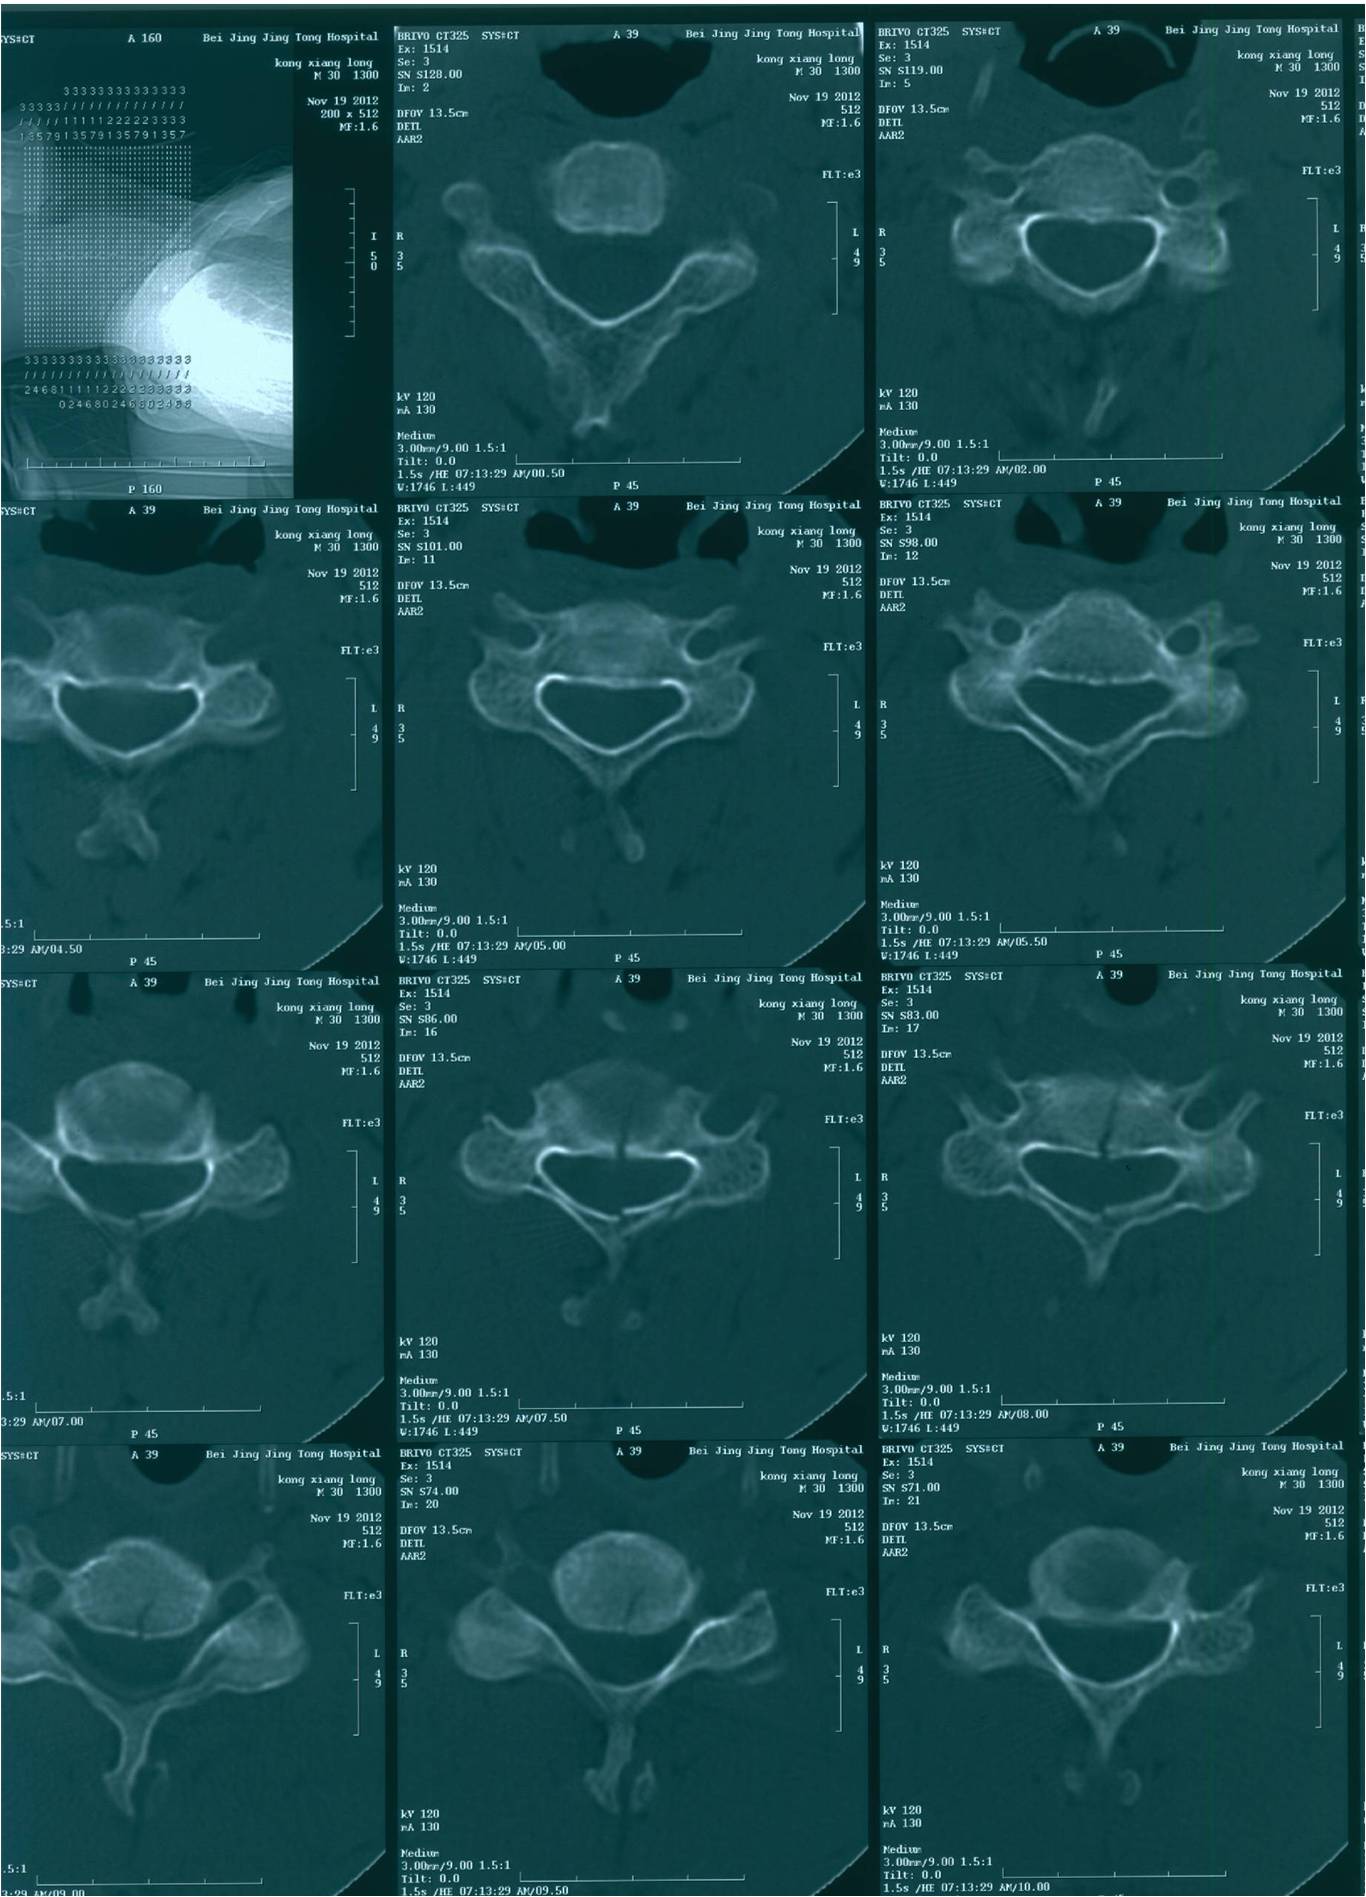

2012-11-18 车祸致四肢感觉、运动及二便功能障碍。

查体:意识清楚,呼吸均匀,查体合作。双侧感觉平面颈4,运动平面颈5. 颈6以下轻触觉保留至肛周,针刺觉消失。颈5以下只有肛门括约肌保留运动功能。下肢肌张力0级。腱反射消失。球海绵体反射可引出。当地医院行X片、CT、MRI检查